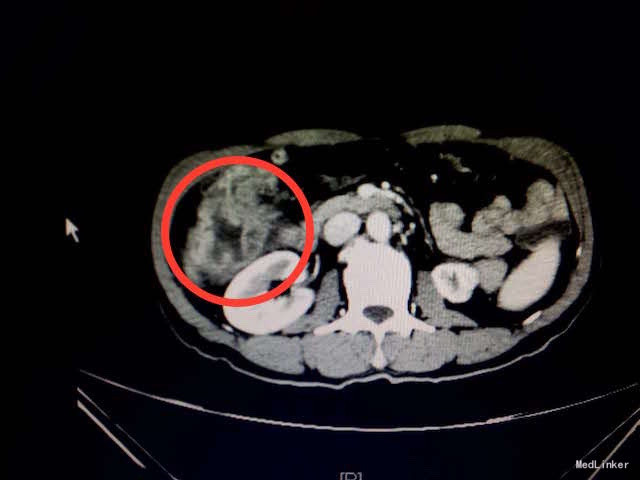

查体:消瘦体型,心肺查体阴性。腹软,右上腹深压痛,无反跳痛,未触及包块,肠鸣音正常。 辅助检查:入院血常规、生化、肝肾功、凝血、传染病未见明显异常。胃肠肿瘤指标正常。大便隐血试验(+)。腹部CT结果:结肠肝曲肠壁局部明显增厚,增强扫描强化明显,考虑恶性肿瘤,累及浆膜层(如下图所示)。